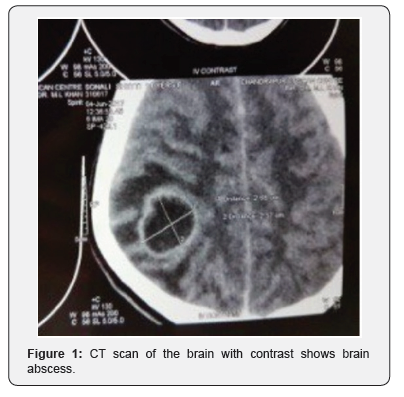

A 12 year female child was referred to our hospital with complaints of headache since 2 months and 2-3 episodes of vomiting since 1 day. Headache was generalized, throbbing in nature, progressively increasing in the last 7 days. Each episode lasted for approx 3-4 hour. Relieved on medication, not associated with any aggravating factors. Headache was associated with vomiting and one episode of convulsion. Vomiting was non projectile in nature, consisting of food particles. No hematemesis and blood in vomitus. Mother gives history of one episode of convulsion with clenching of teeth, frothing from mouth and deviation of angle of mouth to left side, lasting for 1-2 minutes with no postictal drowsiness. There was no history of fever, diplopia, slurring speech, sinusitis, ear discharge or head injury or any other neurological deficit. On 7th day of illness CT scan brain with contrast done from outside which was suggestive of brain abscess (Figure 1).

In our case culture was sterile and the causative organism is not known. CT Brain finding of cerebritis in early stages are characterised by a parenchymal low density lesion [2]. In later stages the typical finding is a hypodense lesion with thin uniform ring enhancement on contrast CT imaging. MRI Brain with gadolinium on T1 weighted images brain abscess appears as a hypointense lesion with ring enhancement. On T2 weighted images it appears as a central hyperintense lesion encircled by a uniform hypointense capsule and surrounded by an irregular hyperintense area of perilesional edema [3,13].